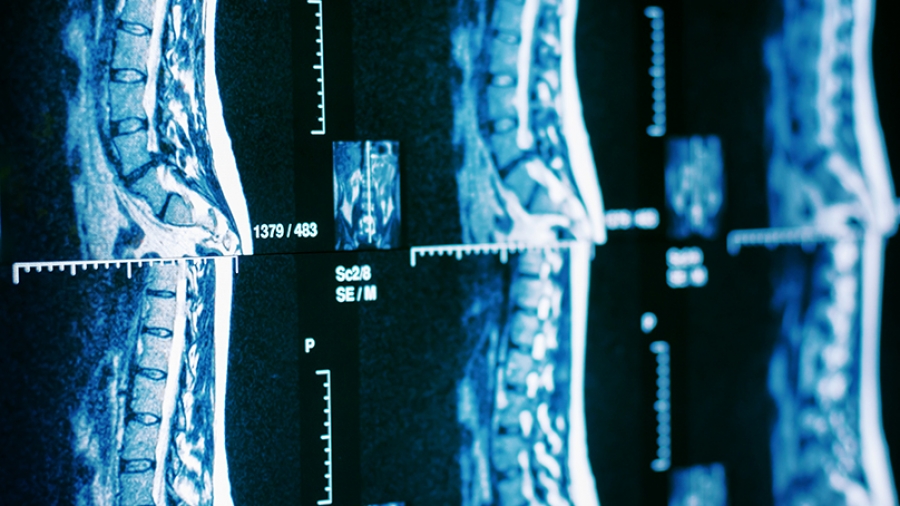

Το σχέδιο του χειρουργού στηρίζεται σε μια αξονική τομογραφία που γίνεται πριν ή κατά το χειρουργείο και φορτώνεται στον υπολογιστή του ρομπότ

Το σχέδιο του χειρουργού στηρίζεται σε μια αξονική τομογραφία που γίνεται πριν ή κατά το χειρουργείο και φορτώνεται στον υπολογιστή του ρομπότ. Κατά τη διάρκεια της χειρουργικής επέμβασης, το ρομπότ διευκολύνει το σχέδιο επισημαίνοντας το σημείο εισαγωγής των εμφυτευμάτων.